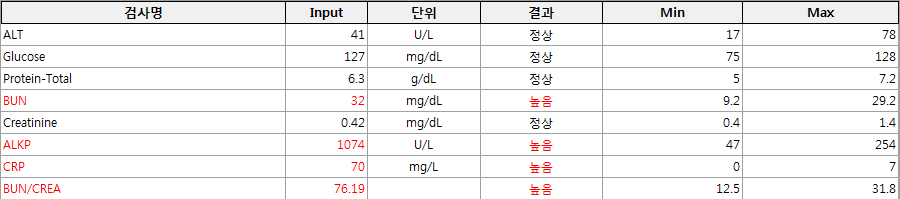

마취의 위험을 줄이기 위해 꼼꼼한 검사와 수액처치 후 호흡마취로 수술에 들어갑니다.

자궁축농증의 점과 어린이의 나이를 고려하여 혈액 검사 결과를 체크하고, 신중하게 마취를 하여 수술을 마쳤습니다.

자궁 내의 고름 때문에 자궁이 팽창하고 있고, 체내의 염증치도 꽤 높은 상태입니다.

자궁과 난소를 완전히 적출하는 수술 후 상태가 안정되면 며칠 내에 수치가 안정됩니다.

이는 검사상의 수치와 식욕 증가 및 활력의 정상화 등 전반적인 상태의 호전에서도 확인할 수 있습니다.